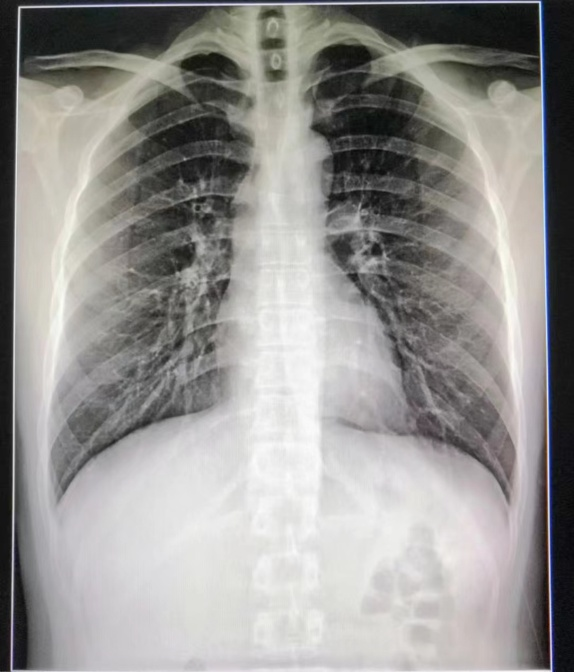

DR全称为数字化X线摄影,就是老百姓口中的平片。是日常大家接触较多的一项检查,它是利用X线的穿透能力成像,检查时就像给身体内部拍了一张平面影像的照片,由于被照物体密度的不均匀,拍摄之后的底片上会形成黑白不一的颜色,所以我们经常能看出片子上骨头的位置颜色偏白色,软组织则显像不清。

优点:适用人群较广,成像速度快,且价格相对较便宜,便于临床重症、急症患者的诊治。

缺点:DR受制于身体组织影响,影像可能会存在重叠和隐藏的情况,有时需要多次或多角度拍摄才能看清。

DR成像也容易受衣物、首饰甚至过厚的软组织影响,所以一般作为初步检查使用。